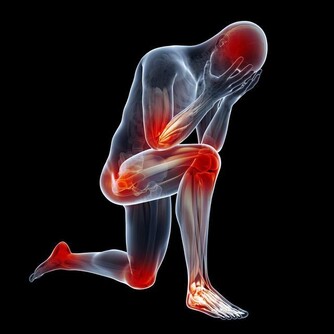

6. 你會感到頭暈、暈眩

鉀的工作任務之一是保持神經系統健康。

當你沒有足夠的鉀時,手臂和腿部會感到刺痛,並且會感到麻木。

而鉀的大幅下降,也會減慢你的心跳,讓你感覺頭暈目眩,好像你會隨時暈倒似的。